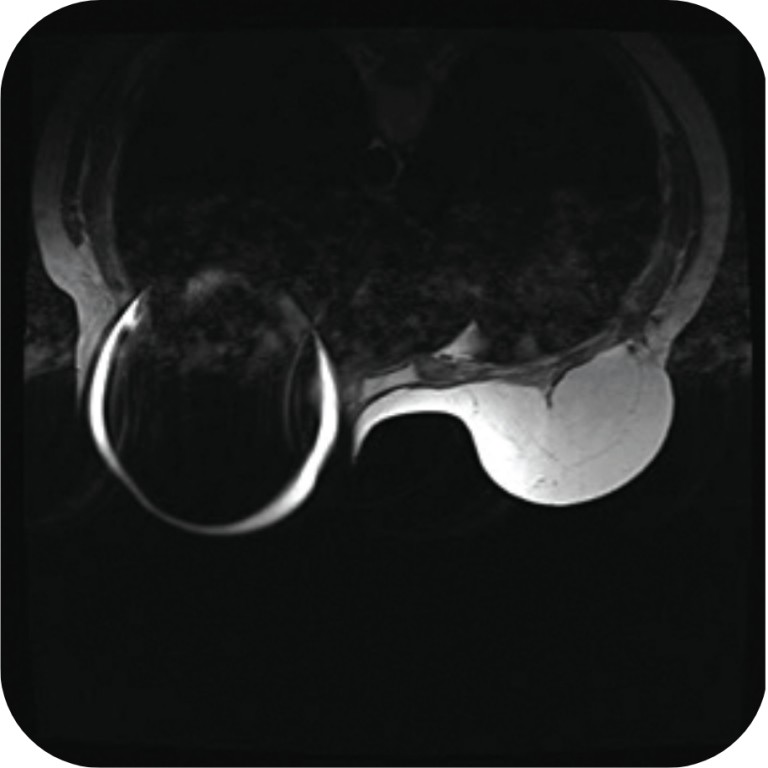

MRI with Motiva Flora® SmoothSilk® Tissue Expander with RFID Port

Motiva Flora® SmoothSilk® Tissue Expanders with the RFID port do not generate distortion of T1 (a) or T2 (b) in weighted axial MRI images*.

MRI with Traditional Magnetic Port

Traditional magnetic ports create large distortions that impede correct assessment of T1 (a) and T2 (b) in weighted axial MRI images, even in the contralateral breast*.

*Reprinted with authorization: Roller R, Chetlen A, Kasales C. J Am Osteopath Coll Radiol. 2014;3(1):2-9. AOCR